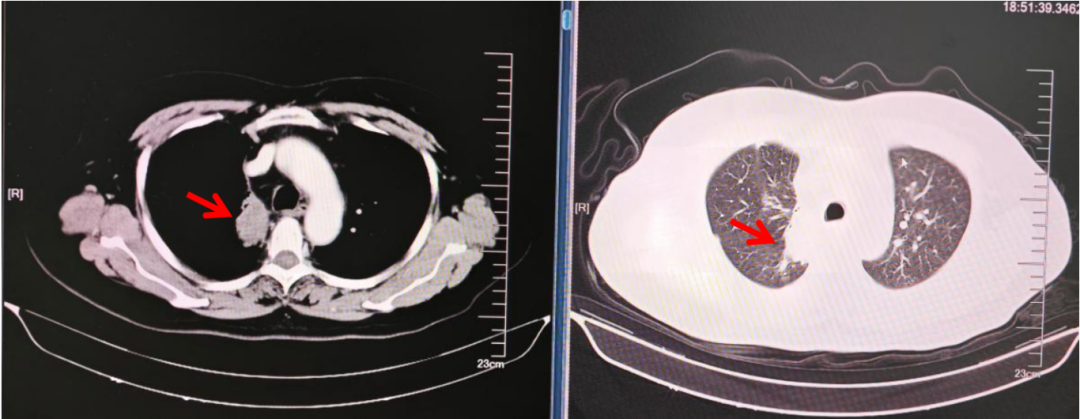

肺恶性肿瘤并胸膜转移胸腹及颈部痛PCA鞘内治疗1例

病史摘要:患者为62岁男性,肺腺癌2年余,右胸背部及颈部疼痛2月余且加重1个月。2022年10月因胸闷、咳嗽确诊肺腺癌,予阿美替尼靶向治疗;2024年5月病理诊断为小细胞肺癌,规律抗肿瘤治疗。2月前出现疼痛,口服阿片类药物,剂量增加但疼痛控制不佳且伴便秘。 诊疗过程:入院NRS评分6分,胸腹部平扫CT及全脊柱MRI提示多处转移可能。诊断为慢性癌痛、右肺恶性肿瘤(IV期)等多种疾病。行鞘内药